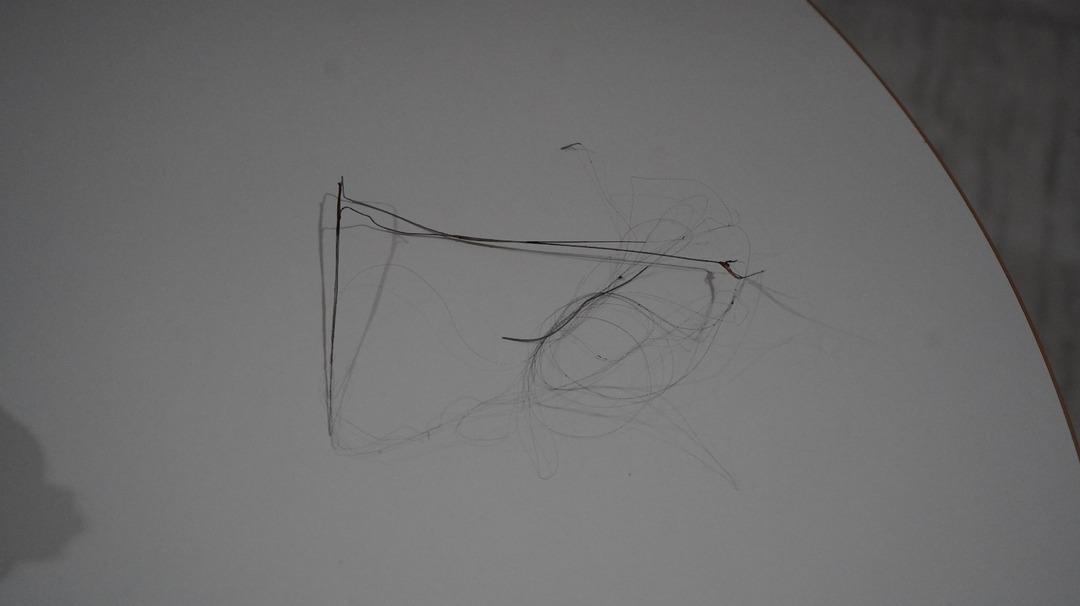

Seamore (37) ve Şaç'ta yaşayan Mehmet Ötün (40), Mayıs ayında bir parça salatalık yuttuktan sonra öksürük ve kusma şikayetleri gözlendiğinde Sernak Eyalet Hastanesine getirildi. Burada, ARAM gövdesinde yarıçap X ve manyetik rezonans görüntüleme unutuldu. Diyarbakir Gazi Yeşargil'in eğitim ve araştırma hastanesi jinekolojiye ve ARAM'lar için ek binaya yönlendirildi, 18 santimetrede 5.5 saatlik riskli cerrahi kaldırıldı. Postoperatif araştırmalarda, kateter kalp kapakına ve karaciğere zarar vermeye kararlıydı.

Aile avukatı Ahmet Yalçın, ikisinin de hastaneden şikayet ettiğini ve bir dava açtığını açıkladı ve şunları söyledi: “Müvekkilim Eylül 2022'de Stevens -Johnson'un kariyeri nedeniyle Eylül 2022'de Dicole'deki üniversite hastanesinde tedavi edildi. Kateter ona saldırıya uğradı.

Otün, oğlunun piknikte bir parça salatalık yuttuktan sonra atmaya ve kusmaya başladığını söyledi: “Oğlum 3 yıl önce Steven Johnson sendromu hastalığında yakalandı. Milyonda görülen bir antibiyotik hastalığı.

“Oğlum yaklaşık 5.5 saat ameliyatta kaldı. Müdahaleye giren doktor olumsuz bir şekilde serbest bırakıldı. Yorgun ve yorgun olduklarını söylüyordu. Materyal geliyor, iplik geliyor, dedi. Bir doktor çıktı, 'İki seçeneğimiz var. Hayatım için çok acı vericiydim.